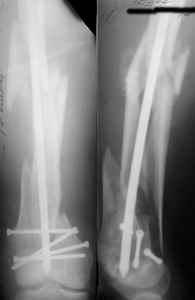

KEMMD> (Alex, do you have one good case in your collection of

KEMMD> anterograde nailing in very distal fractures - as you have

I presented a series of ~25 such cases at EuroTrauma'2004. Many cases were discussed here. I attach am example. Look also recent cases at http://www.hwbf.org/hwb/conf/alex58/scfx.htm,

http://www.hwbf.org/hwb/conf/alex63/alex63.htm

THX, initial images are

1,

2.

At that moment we had in stock only the 10 mm solid nails so of course there was no idea about early weight bearing. But it was quite enough for early knee ROM excersises (see attached). Two locking screws through the distal block provided that.